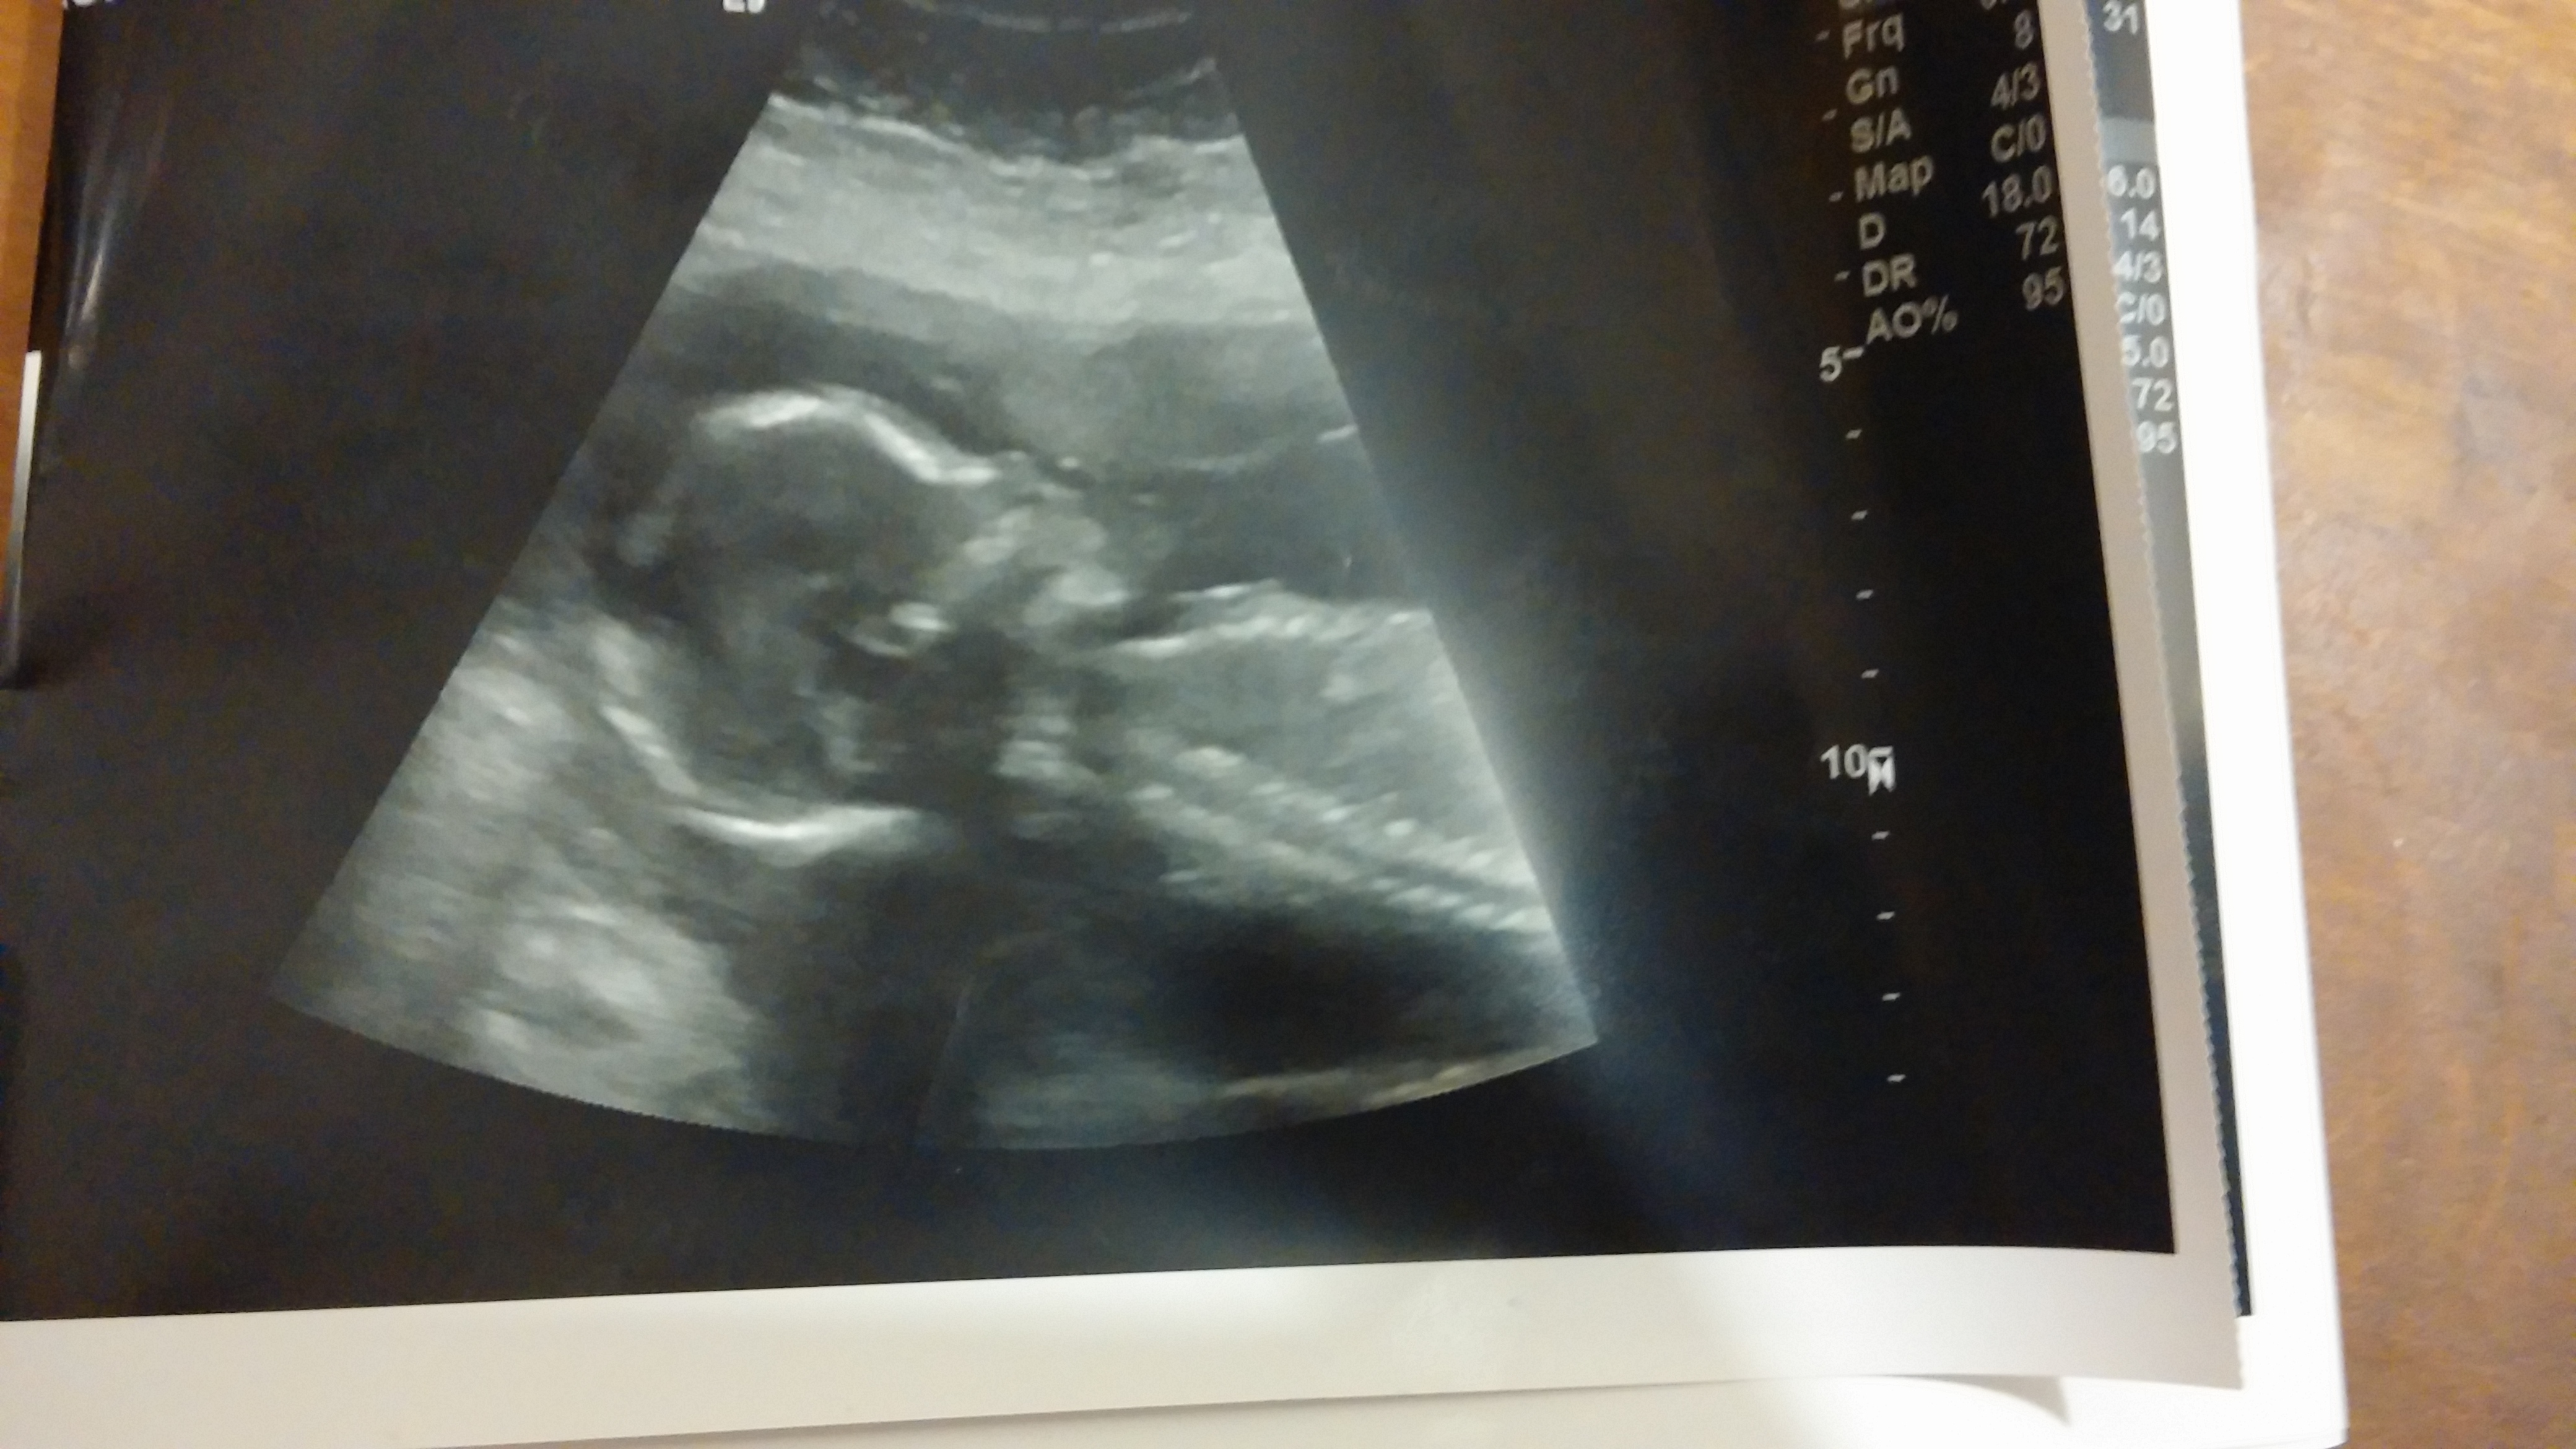

Ok...I need to know if I'm crazy or this something actually feasible. I'm currently 22w 3 days with my 5th baby. I have always had a larger stomach from having 4 c sections. It was from my first that I gained weight and never lost it. So I always look 4-5 months pregnant. Anyways I had an ultrasound at 7weeks. My last 2 sonogram I had to have an on top of the belly scan instead of a vaginal because vaginally you couldn't see anything because my uterus is so high(Dr said possible because I've had many csections). So I was told there was NO chance of twins. So now like I said I'm 22w 3d and I look 8 months pregnant. I had very bad nauseous until about 15 weeks. My mother in law has crazy intuition and is always right about it. She made the comment to me...are you SURE you are not having twins? I said unless the doctor is lying or doesn't see it then yes I'm sure. Ever since then I've noticed that I'm feeling kicks very high and then separately very low. Never at the same time and never in the middle between the 2 areas. I looked back at my 19w ultrasound(attached below) if you notice the obvious baby in the center...underneath there is either an arm and a hand and something else. If it is an arm it's impossible for it to be connected to that baby based on its angle. I felt kicks at 17-18w about 3 inches above my belly button. When the ultrasound tech did the sonogram she never went down low to where I suspect another baby is...they only looked up high. My husband and best friend have seen the sonogram and swear there is another baby in there. I know it's very unlikely to miss a twin with the technology today...but it's not impossible. Since I had my first sonogram early a twin could have appeared weeks following before another sonogram was performed....I know this is possible but I personally know people this has happened to. Also my uterus should be measuring slightly above my belly button at 22weeks I can feek baby kick up to 6 inches above the navel.

Pictures include 19 w sonogram and a pic I took of my belly tonight at 22w 3d.

• Sorry but I see another hand in this other picture. Its a left hand and the baby is at a right profile. Its not possi so for the hand/arm in this pic to be connected to the baby I'm seeing. I'm definitely not leaving it alone and need to investigate further.

• I can see what you think could be a hand, especially in that second ultrasound pic, and out of curiosity I would ask the OB what it is. However, I would be really surprised if it's another baby, mostly because I don't see how one baby could be waving an arm about so closely to the baby they were scanning and a trained tech not notice another baby moving about.

• I see what you could mistake for an arm/hand, but if it were, that would mean that the twin would be in the same sac as the baby pictured. There is no way they would have missed a twin sharing a gestational sac. MAYBE they could miss a twin in a separate sac (highly unlikely, but possible), but then you wouldn't see an arm that close to the other baby (they would be separated by their sacs).